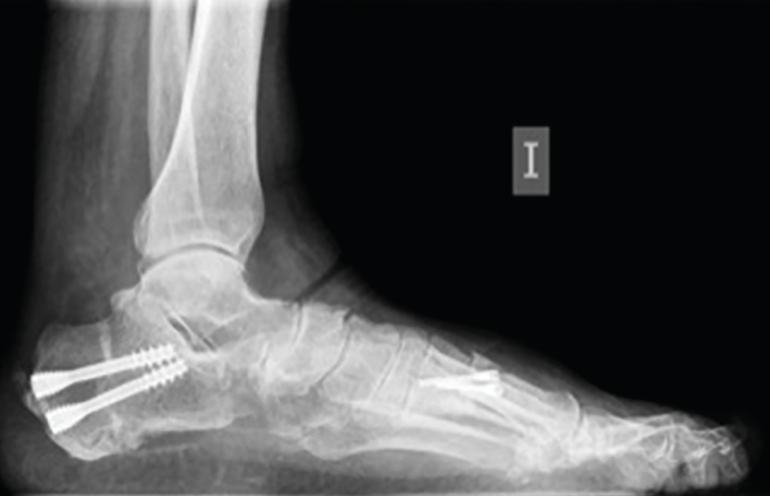

La OPC se realiza bajo anestesia general o regional junto con un bloqueo nervioso anestésico. Se debe tener en cuenta que este procedimiento es tan solo una parte de un conjunto de gestos quirúrgicos destinados a corregir la deformidad, fundamentalmente del pie cavo o pie plano (Figura 1).

Figura 1. Radiografía en carga prequirúrgica.

Figura 10. Radiografía en carga a los 2 meses de la cirugía.

Los procedimientos que acompañan a la OCP en la corrección de las deformidades suelen marcar el tiempo de descarga e inmovilización. Cuando la osteotomía es el único procedimiento óseo de la corrección, se autoriza una carga protegida con bota de tipo Walker e inicio de ejercicios de flexoextensión de tobillo a las 4-5 semanas, para posteriormente iniciar progresivamente la carga completa 2 semanas después (Figuras 10 y 11).

Figura 11. Detalle de la osteotomía en la tomografía computarizada a los 3 meses.